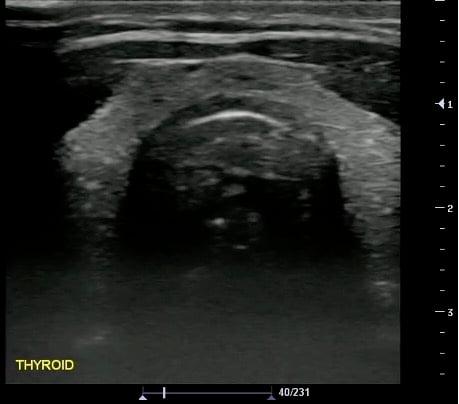

- Normal Thyroid Isthmus and Bilateral Lobes

- Figure 31 and 32. Thyroid

- Normal findings

- Homogeneous ground-glass appearance

- Hyperechoic relative to adjacent muscles

- Obtained in 3 dimensions (anteroposterior, transverse, and longitudinal)

- Nodule > 10 mm concerning for malignancy (controversial; not the only criteria)

- Additional measurements: Isthmus thickness (Transverse > 5mm abnormal), Lobe volume (Width x Length x Depth x 0.5)